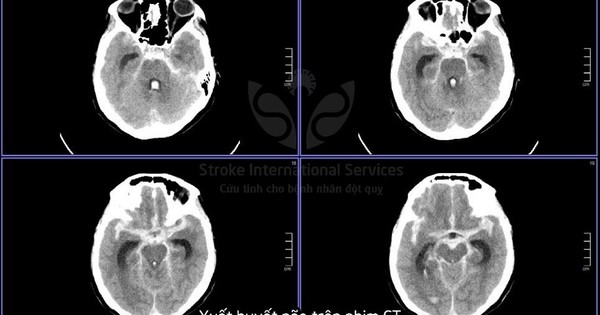

Tại S.I.S Cần Thơ, bà S. được đưa lên phòng DSA để can thiệp khẩn do vỡ phình mạch máu não. BSCKII Nguyễn Lưu Giang, Trưởng đơn vị can thiệp DSA S.I.S Cần Thơ, cho biết bệnh nhân vào viện với tình trạng hôn mê sâu, xuất huyết não nặng do vỡ phình dị dạng mạch máu não.

“Bà S. bị xuất huyết khoang dưới nhện, nếu không kịp thời cấp cứu khả năng tử vong lên đến hơn 90%. May mắn bệnh nhân đến còn trong “thời gian vàng” nên khả năng hồi phục khả quan”-BS Giang thông tin thêm.